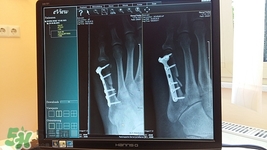

如果發(fā)生尾椎骨折,可以到醫(yī)院找骨科醫(yī)生進(jìn)行手法復(fù)位治療.手法復(fù)位可以不手術(shù)切開,通過通過推,拿,按,摩,摸接,端,提等一系列手法讓脫位或者骨折斷端恢復(fù)原來正常的解剖位置,非常方便、安全.